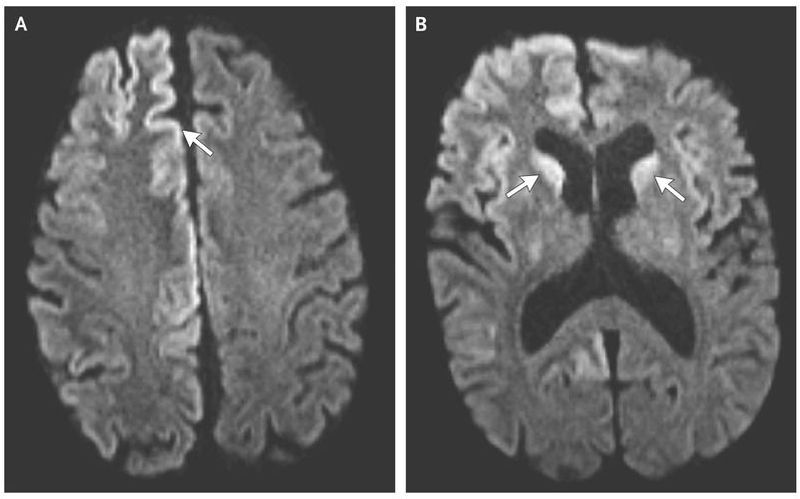

A 54-year-old man presented to the emergency department with a 3-week history of cognitive deterioration and functional decline. He was disoriented, inattentive, and disinhibited. Neurologic examination revealed horizontal gaze-evoked nystagmus, hyperreflexia on the left side, startle myoclonus, and ataxia. Magnetic resonance imaging (MRI) revealed hyperintensity of the cortical gyri of the frontal and occipital lobes, called cortical ribboning (Panel A, arrow), and within the caudate heads on both sides (Panel B, arrows) on diffusion-weighted imaging. Electroencephalography revealed lateralized periodic discharges in the right hemisphere without evidence of seizures. Testing of cerebrospinal fluid was positive for 14-3-3 and tau proteins, which are known markers of prion disease, and the real-time quaking-induced conversion assay, which is highly sensitive for the detection of the abnormal form of the prion protein, was also positive. Given the patient’s rapid clinical deterioration, imaging findings, and cerebrospinal fluid markers, he received a diagnosis of Creutzfeldt–Jakob disease, a fatal spongiform encephalopathy that is caused by the accumulation of abnormal prions. Creutzfeldt–Jakob disease leads to cognitive decline and is characterized by additional neurologic features that manifest according to the location of lesions. Common MRI findings include hyperintensity of the cortex, pulvinar and dorsomedial thalamic nuclei, and basal ganglia on T2-weighted, diffusion-weighted, and fluid-attenuated inversion recovery sequences. The patient died in hospice 8 weeks after the initial onset of symptoms.